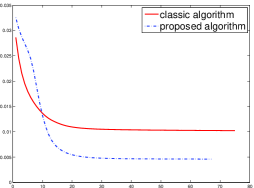

In order to compare the convergent speed of the proposed algorithms with the classic algorithms visually, we present the evolution of MSE along with the iteration process in Fig. 4 for the 3 projection data. And we can observe that the proposed perturbation can accelerate the convergent rate and improve the reconstructed image qualities.